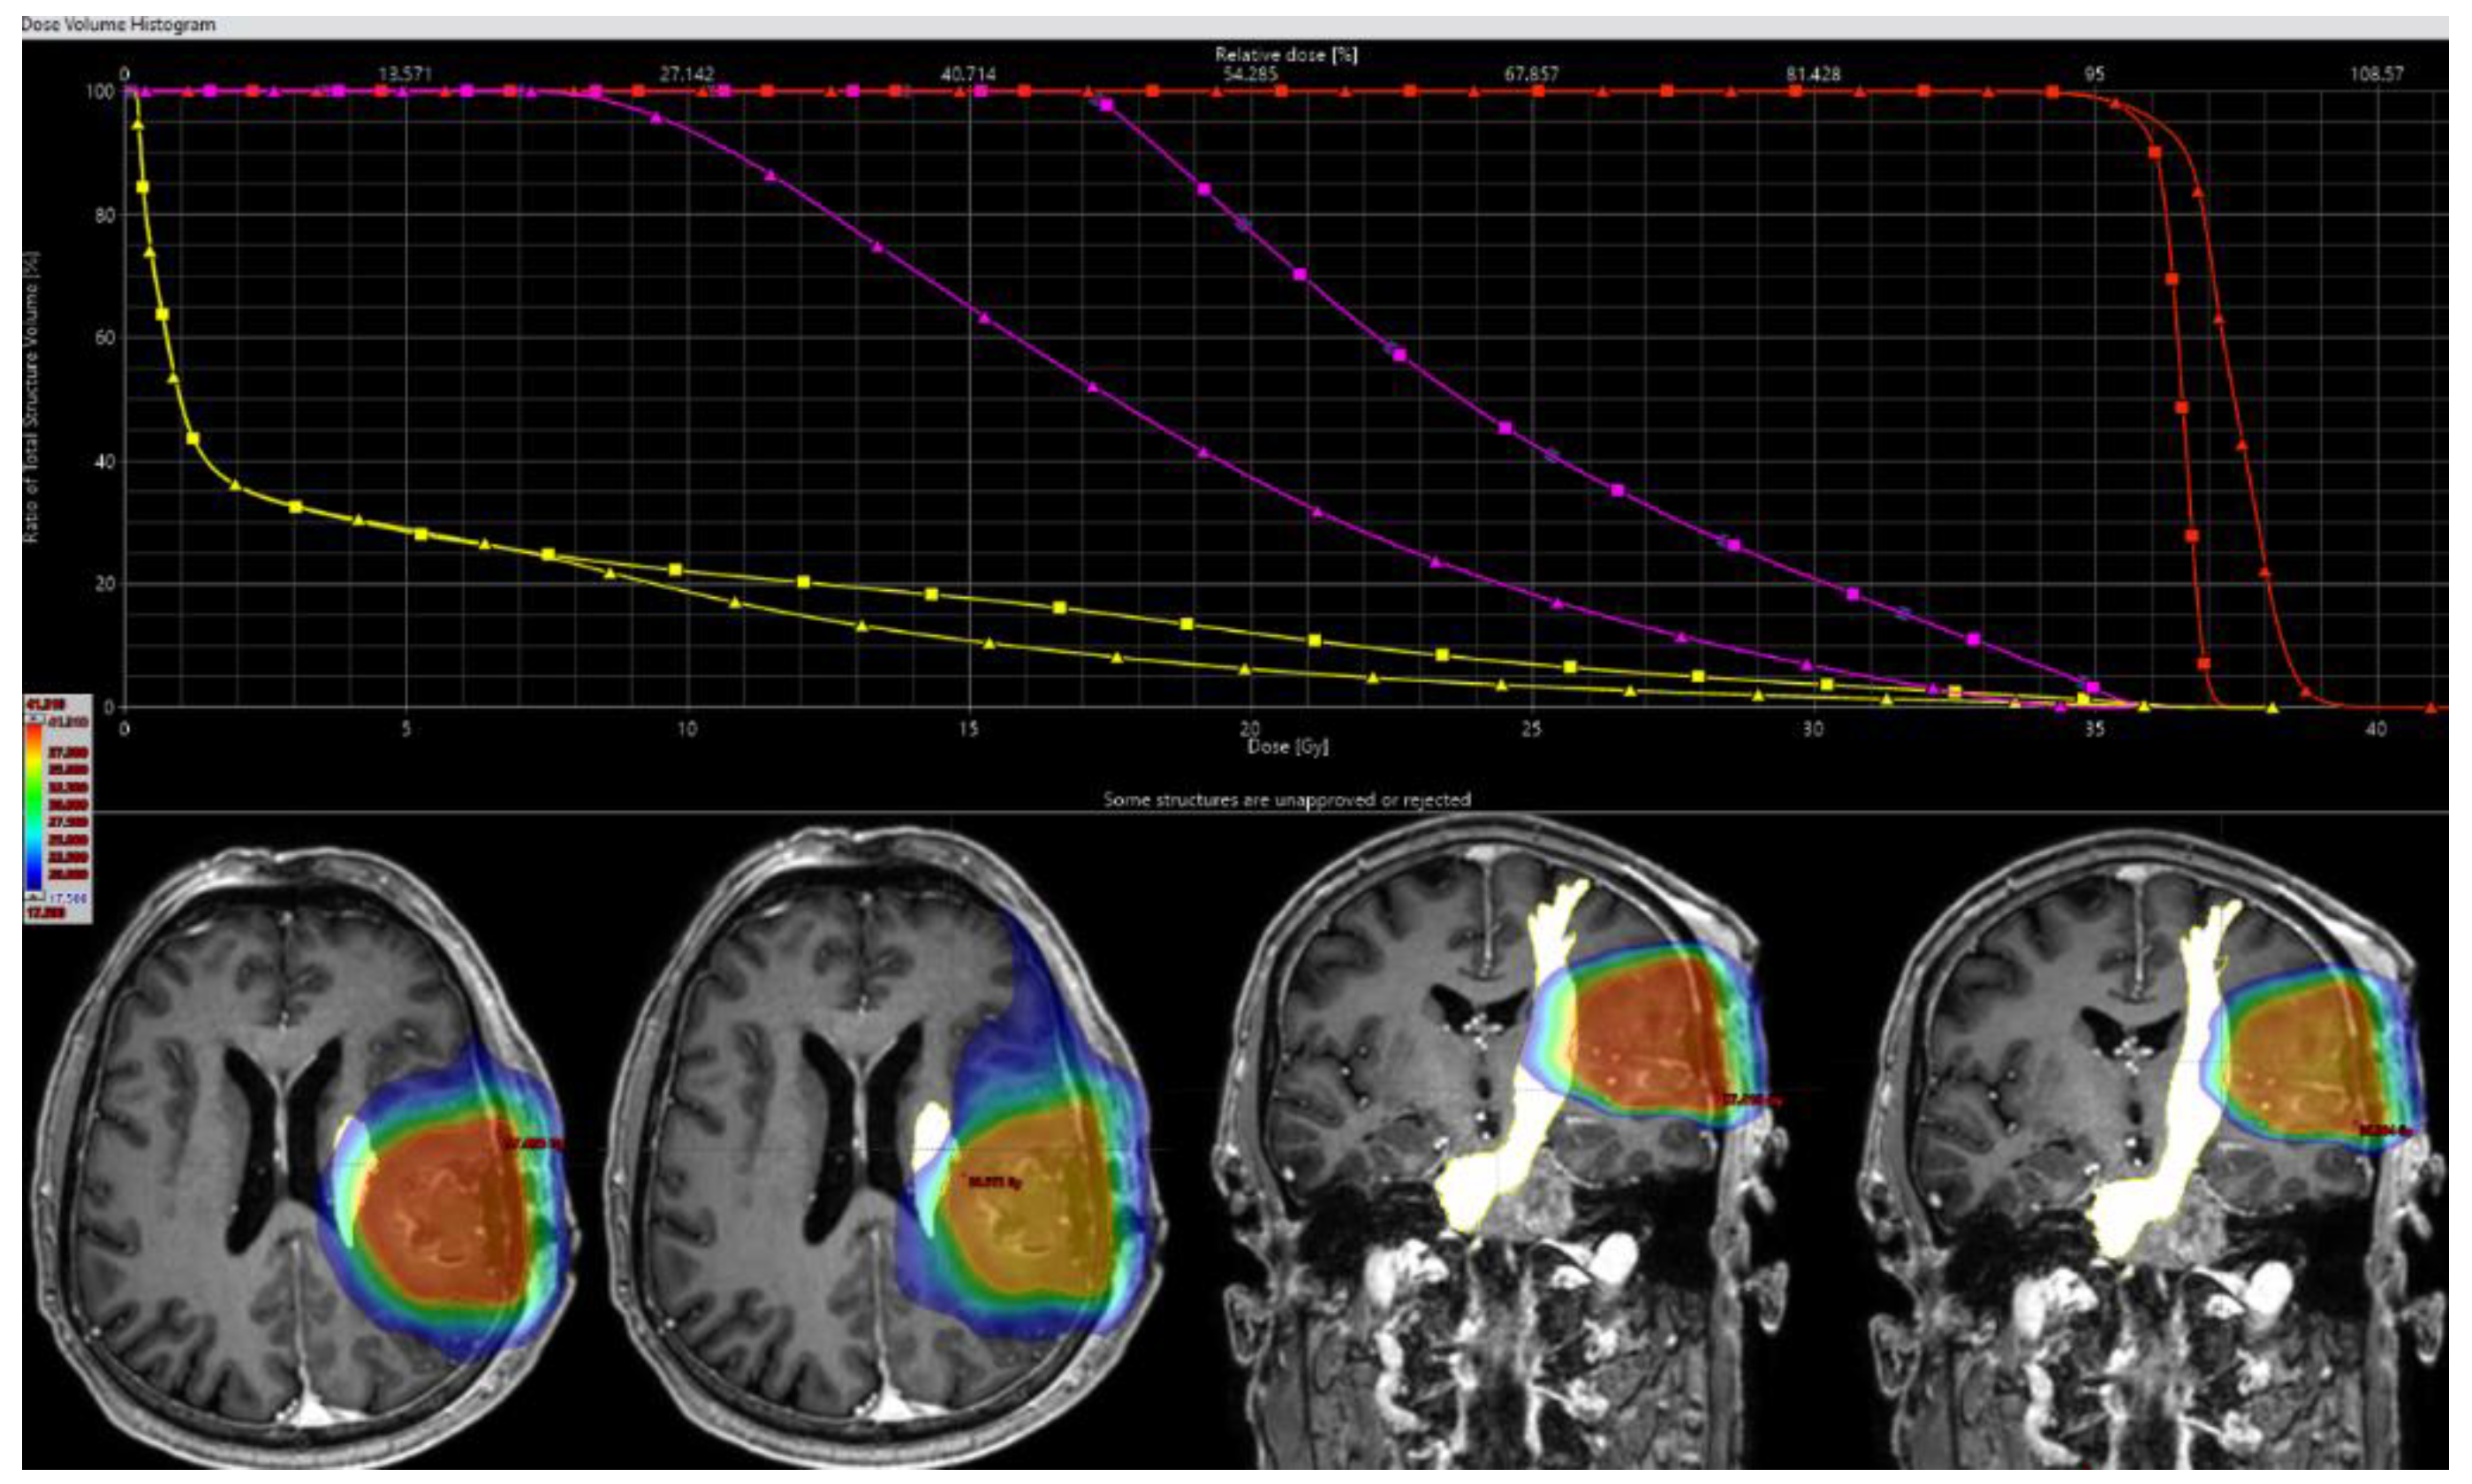

2.5. Target Delineation and Radiotherapy Planning

2.6. Dosimetric Analysis and Comparative Evaluation

3.2. FTmot.TMS Dose Statistics

3.3. PTV Coverage, Conformity, and Outcome